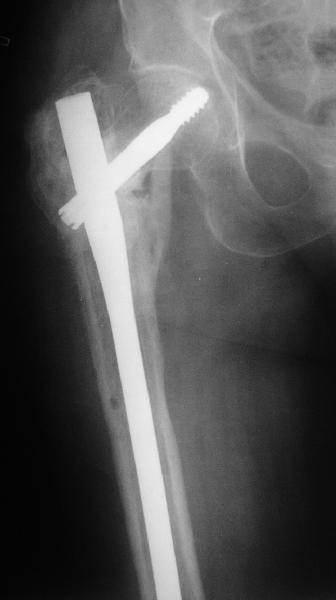

В приложении пример пациента, близкого по картине к тому, что представил Виктор (варус и смещение периферического отломка на поперечник кзади). Сделали как раз то, что Виктор исходно намеревался - аппаратная коррекция и затем гамма.

По опыту подобных случаев, аппарат лучше на бедро, без таза пока. В проксимальный фрагмент 3 стержня по оси шейки. Дистальный - хватит 1 стержня или 2 спиц в дистальном метафизе и 1 стержня вверху. Если планируете гвоздь, надо с гиперкоррекцией восстановить длину и ось, т.е. вальгизировать проксимальный отдел. При наложении аппарата сделать остеоклазию, добиться уверенной подвижности. Регенерат не нужен, тяните на пределе переносимости пациентом - хоть 2 см/сут. Обычно меньше.

Второй этап - на следующий день после окончания коррекции.

Если все получилось, т.е. закрыто сопоставить с гиперкоррекцией, накладываете дистрактор таз-бедро или используете тракционный стол, и гвоздь можно делать закрыто. Пластика то есть не нужна. Если клинковая пластина - может получиться как при меежвертельной остеотомии, боковая компрессия by mismatch. Тогда тоже пластика не нужна. Если не получатся, можно и сделать.